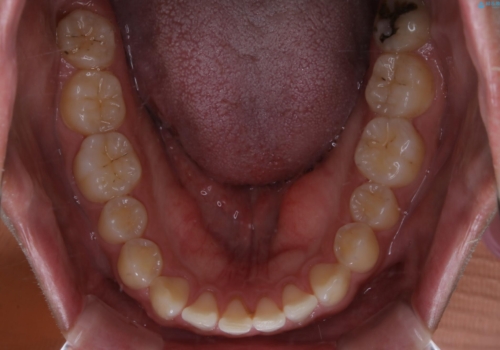

- 上のすきっ歯が気になるとご相談にいらした方です。上下顎ともにスペースがあったため、インビザラインFULLにて見た目と噛み合わせの改善も同時に行いました。

元々は上前歯のみの部分矯正をご希望されていましたが、下の歯もスペースがあり、噛み合わせ的にも上のみの部分治療は難しいことをお話ししました。前歯のみの部分矯正を行った場合、前歯の隙間だけが閉じて奥歯が噛めなくなってしまう場合もあります。インビザラインFULLにて治療することで、噛み合わせと見た目を同時に改善させることができ、大変喜んでいただけました。